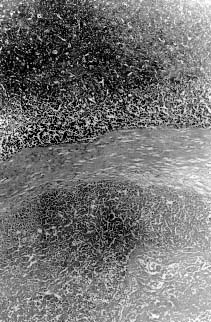

Fig. 1. Large areas of necrosis scattered throughout the tumor forming lobules surrounded by well-defined fibrous strands. 62.5 x, H&E.   Fig. 2. Mitotic figures observed at high power field. 500 x H&E.

Microscopically, the mass was composed of closely packed ribbons and nests of large round to polygonal cells with low amounts of basophilic cytoplasm and large round nuclei with prominent nucleoli divided into demarcated lobules by delicate septa of fibrous tissue. Large areas of necrosis werescattered throughout the mass forming lobules surrounded by well-defined fibrous strands (Fig. 2). The morphology of the tumor cells was consistent with a seminoma. In addition, clusters of small round to oval eosinophilic cells with condensed round nuclei were observed occasionally in the middle of some lobules. A minimum amount of hemorrhage was also observed.